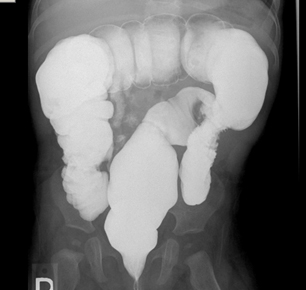

Enema: um enema de bário é útil para o diagnóstico de atresia do intestino delgado ou da doença de Hirschsprung; um enema diagnóstico pode ser usado para auxiliar no diagnóstico de intussuscepção e também agir como intervenção terapêutica.[Figure caption and citation for the preceding image starts]: Enema de bário com zonas de transição em pacientes com doença de HirschsprungDos acervos do Dr. R.A. Gomez-Suarez e Dr. J.E. Fortunato; usado com permissão [Citation ends].